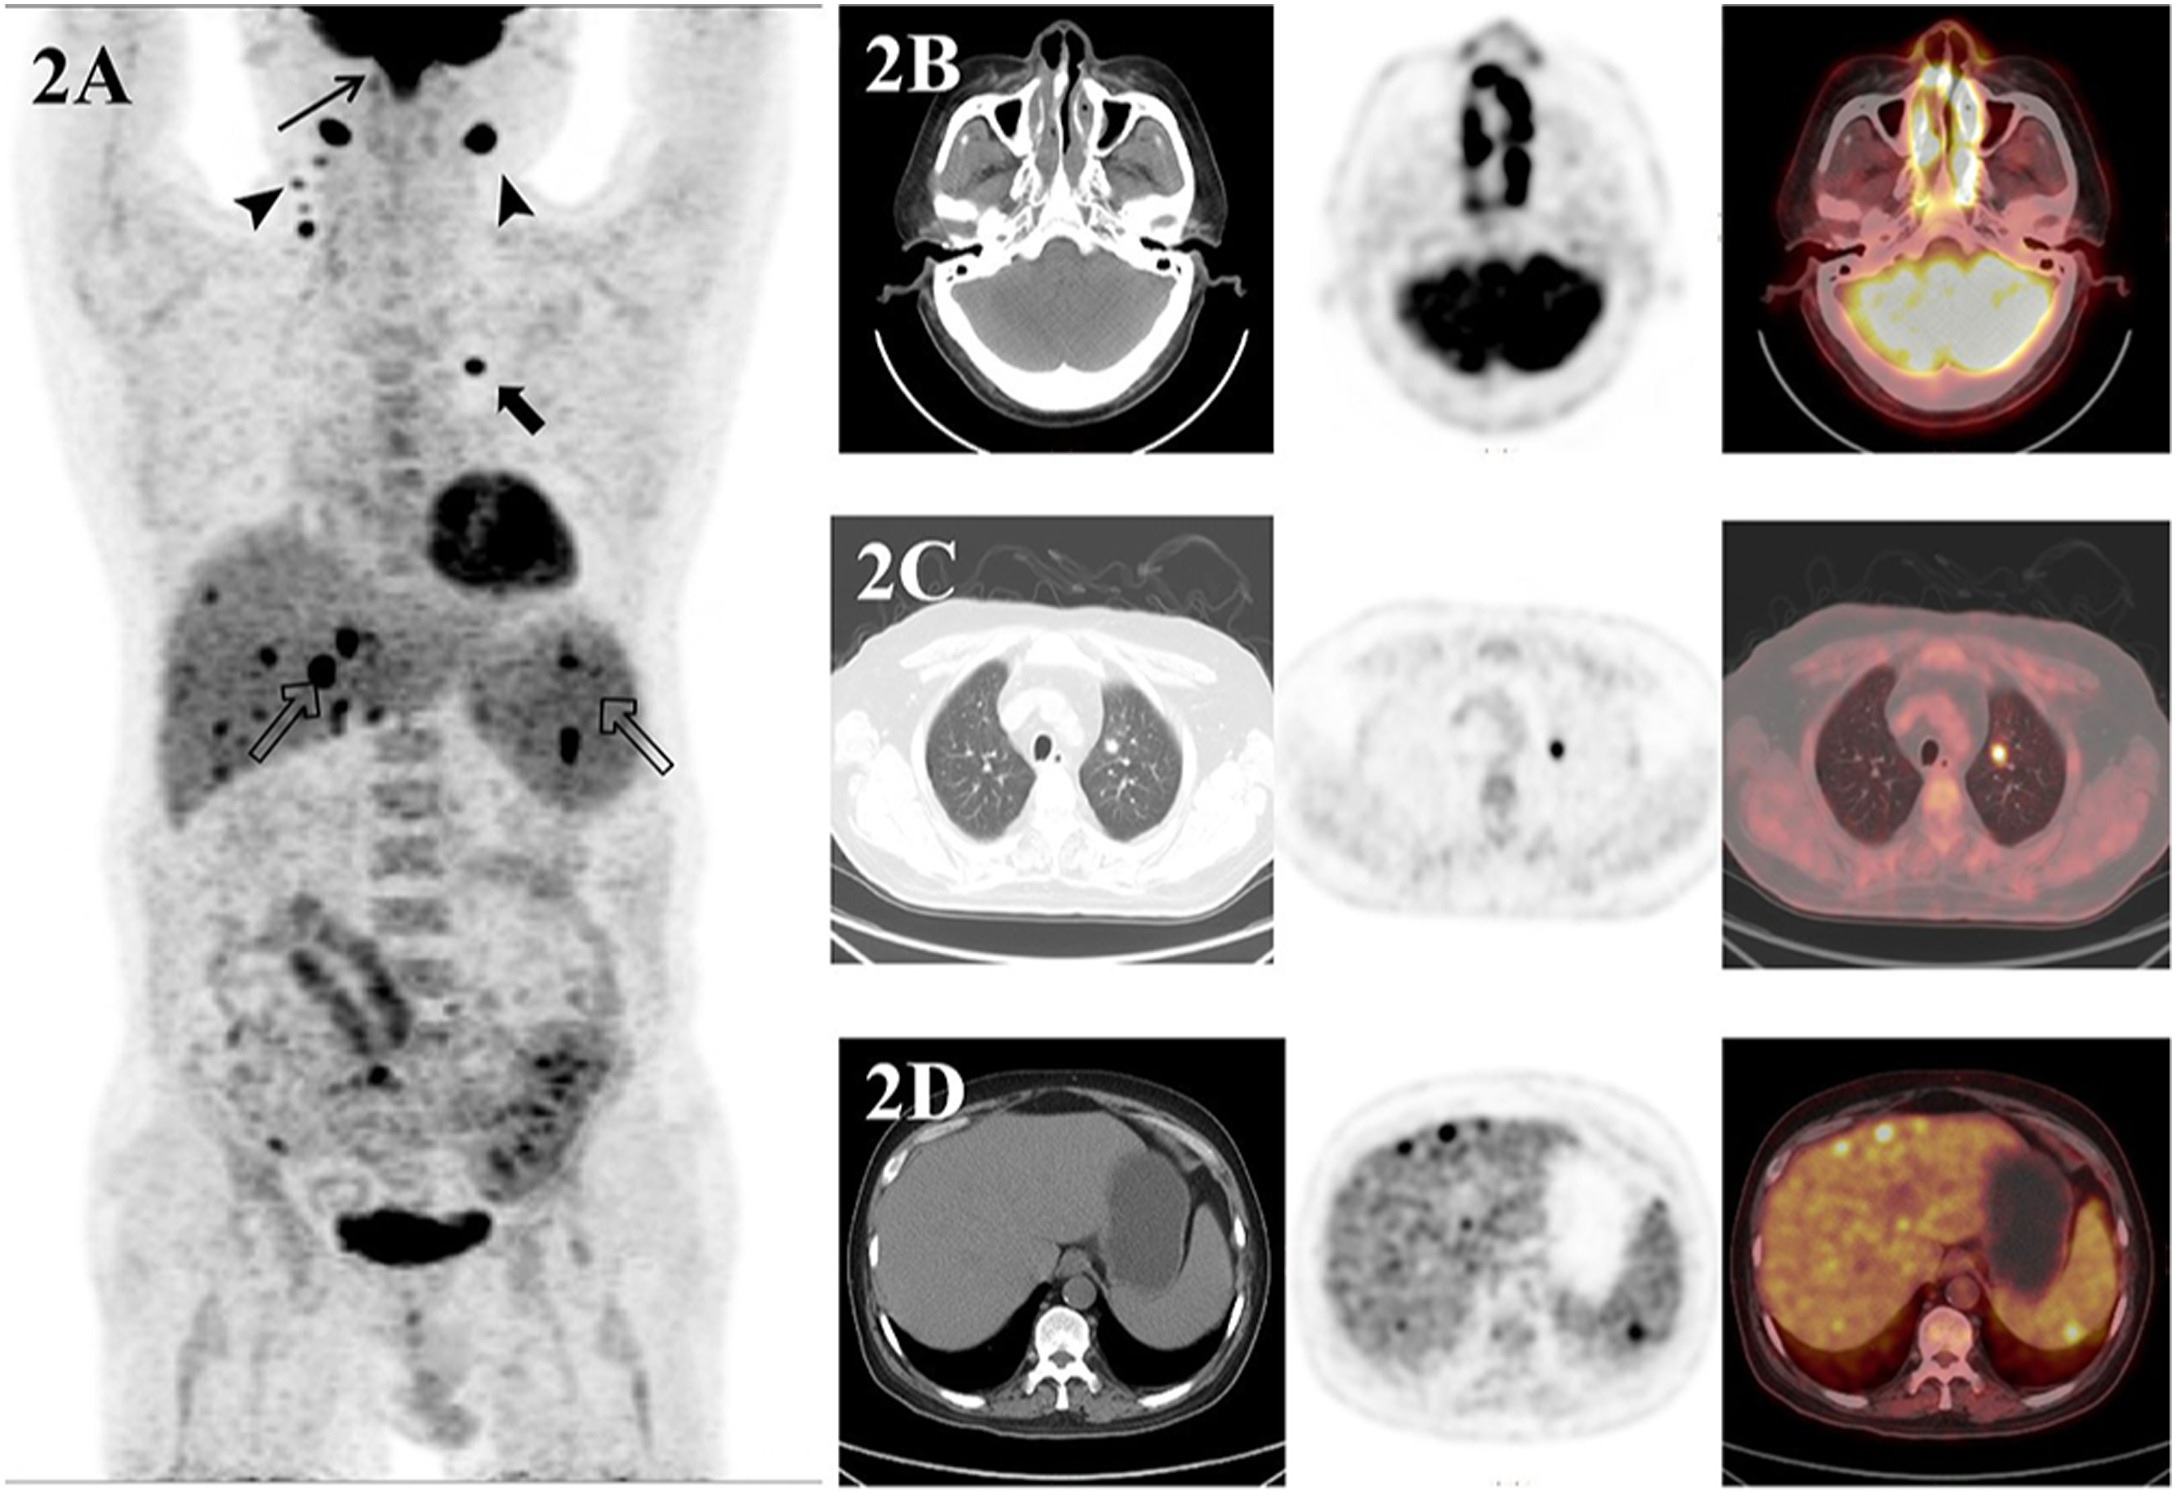

- PET/CT scans ‘crucial’ in patients with NK/T-cell lymphoma